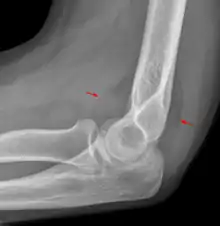

A subtle radial head fracture with associated positive sail sign